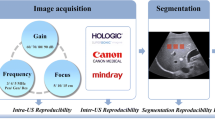

Three-dimensional turbo spin echo T1-weighted imaging was performed in 14 healthy volunteers (mean age, 57 years; range, 33–67 years; 7 men) under SENSE and CS with accelerator factors of 5.5, 6.8, and 9.7. Eight anatomical locations (brain parenchyma, salivary glands, masseter muscle, tongue, pharyngeal mucosal space, eyeballs) were evaluated. Reproducibility of radiomic features was evaluated by calculating concordance correlation coefficient (CCC) in reference to the original image (SENSE with acceleration factor of 3.5). Reproducibility of radiomic features among acceleration factors and between SENSE and CS was compared.